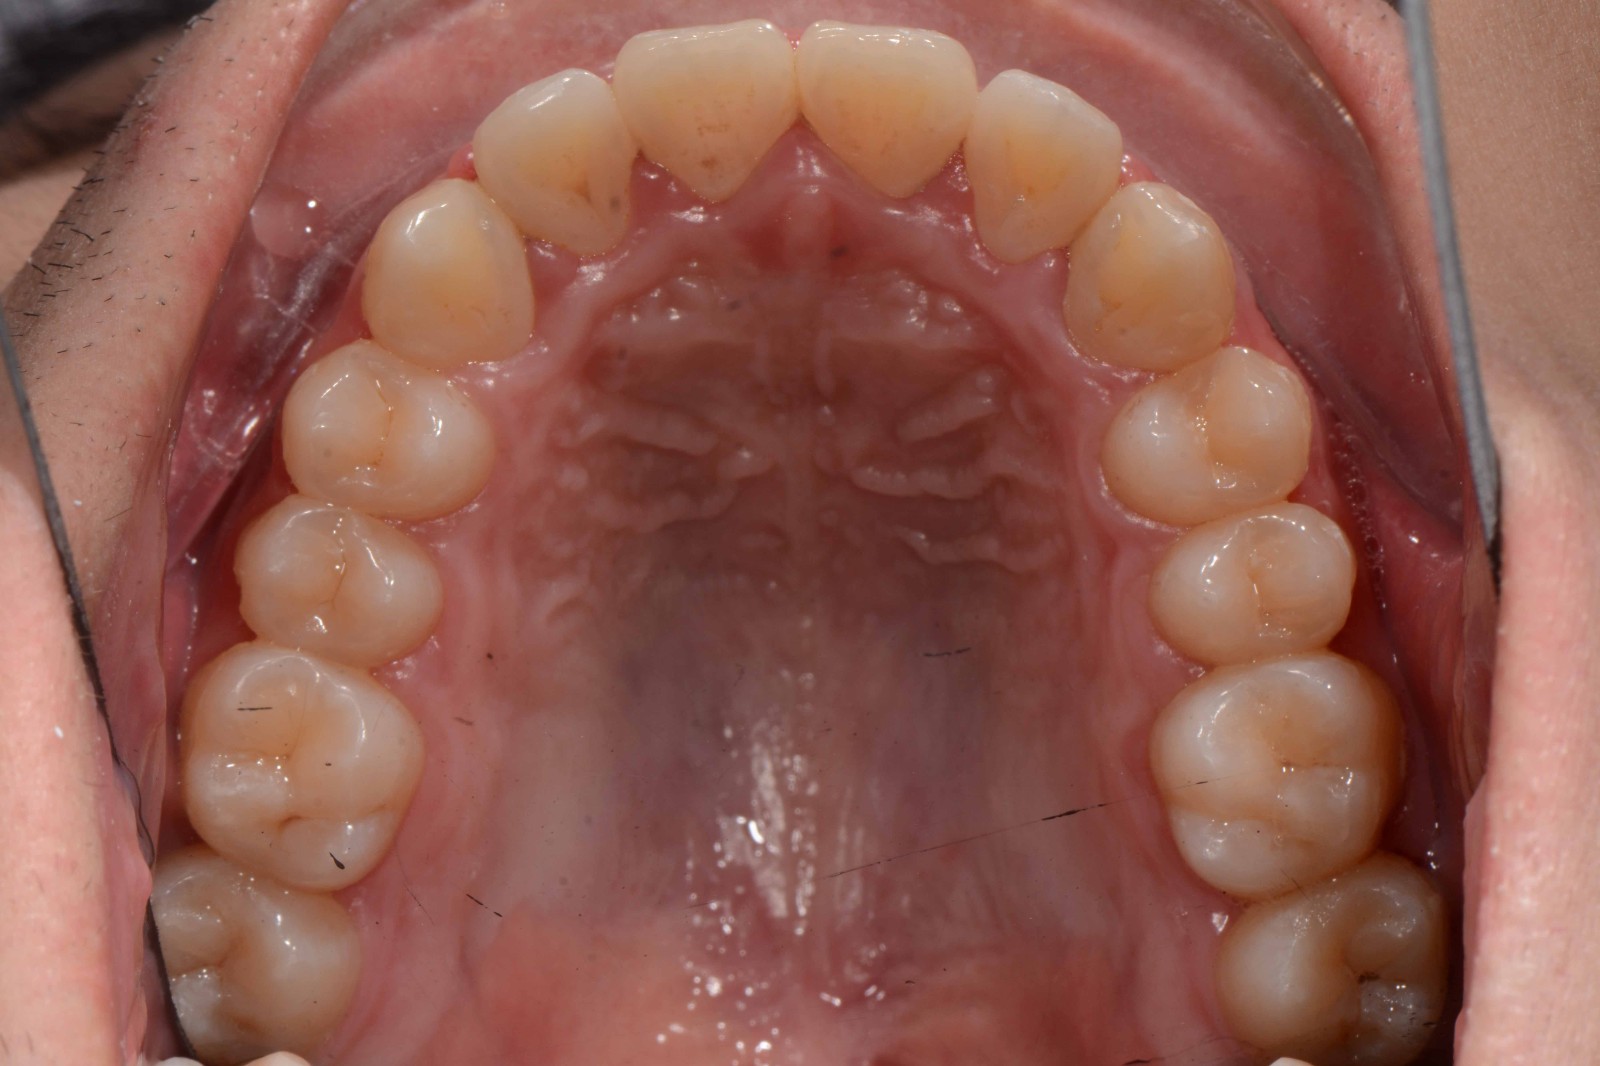

检查:拍摄口内面像照片,拍摄全景片侧位片,口扫,上下颌I-II度拥挤,中线不齐,局部反合,磨牙基本中性关系,上下前牙比较直立。

矫治前: